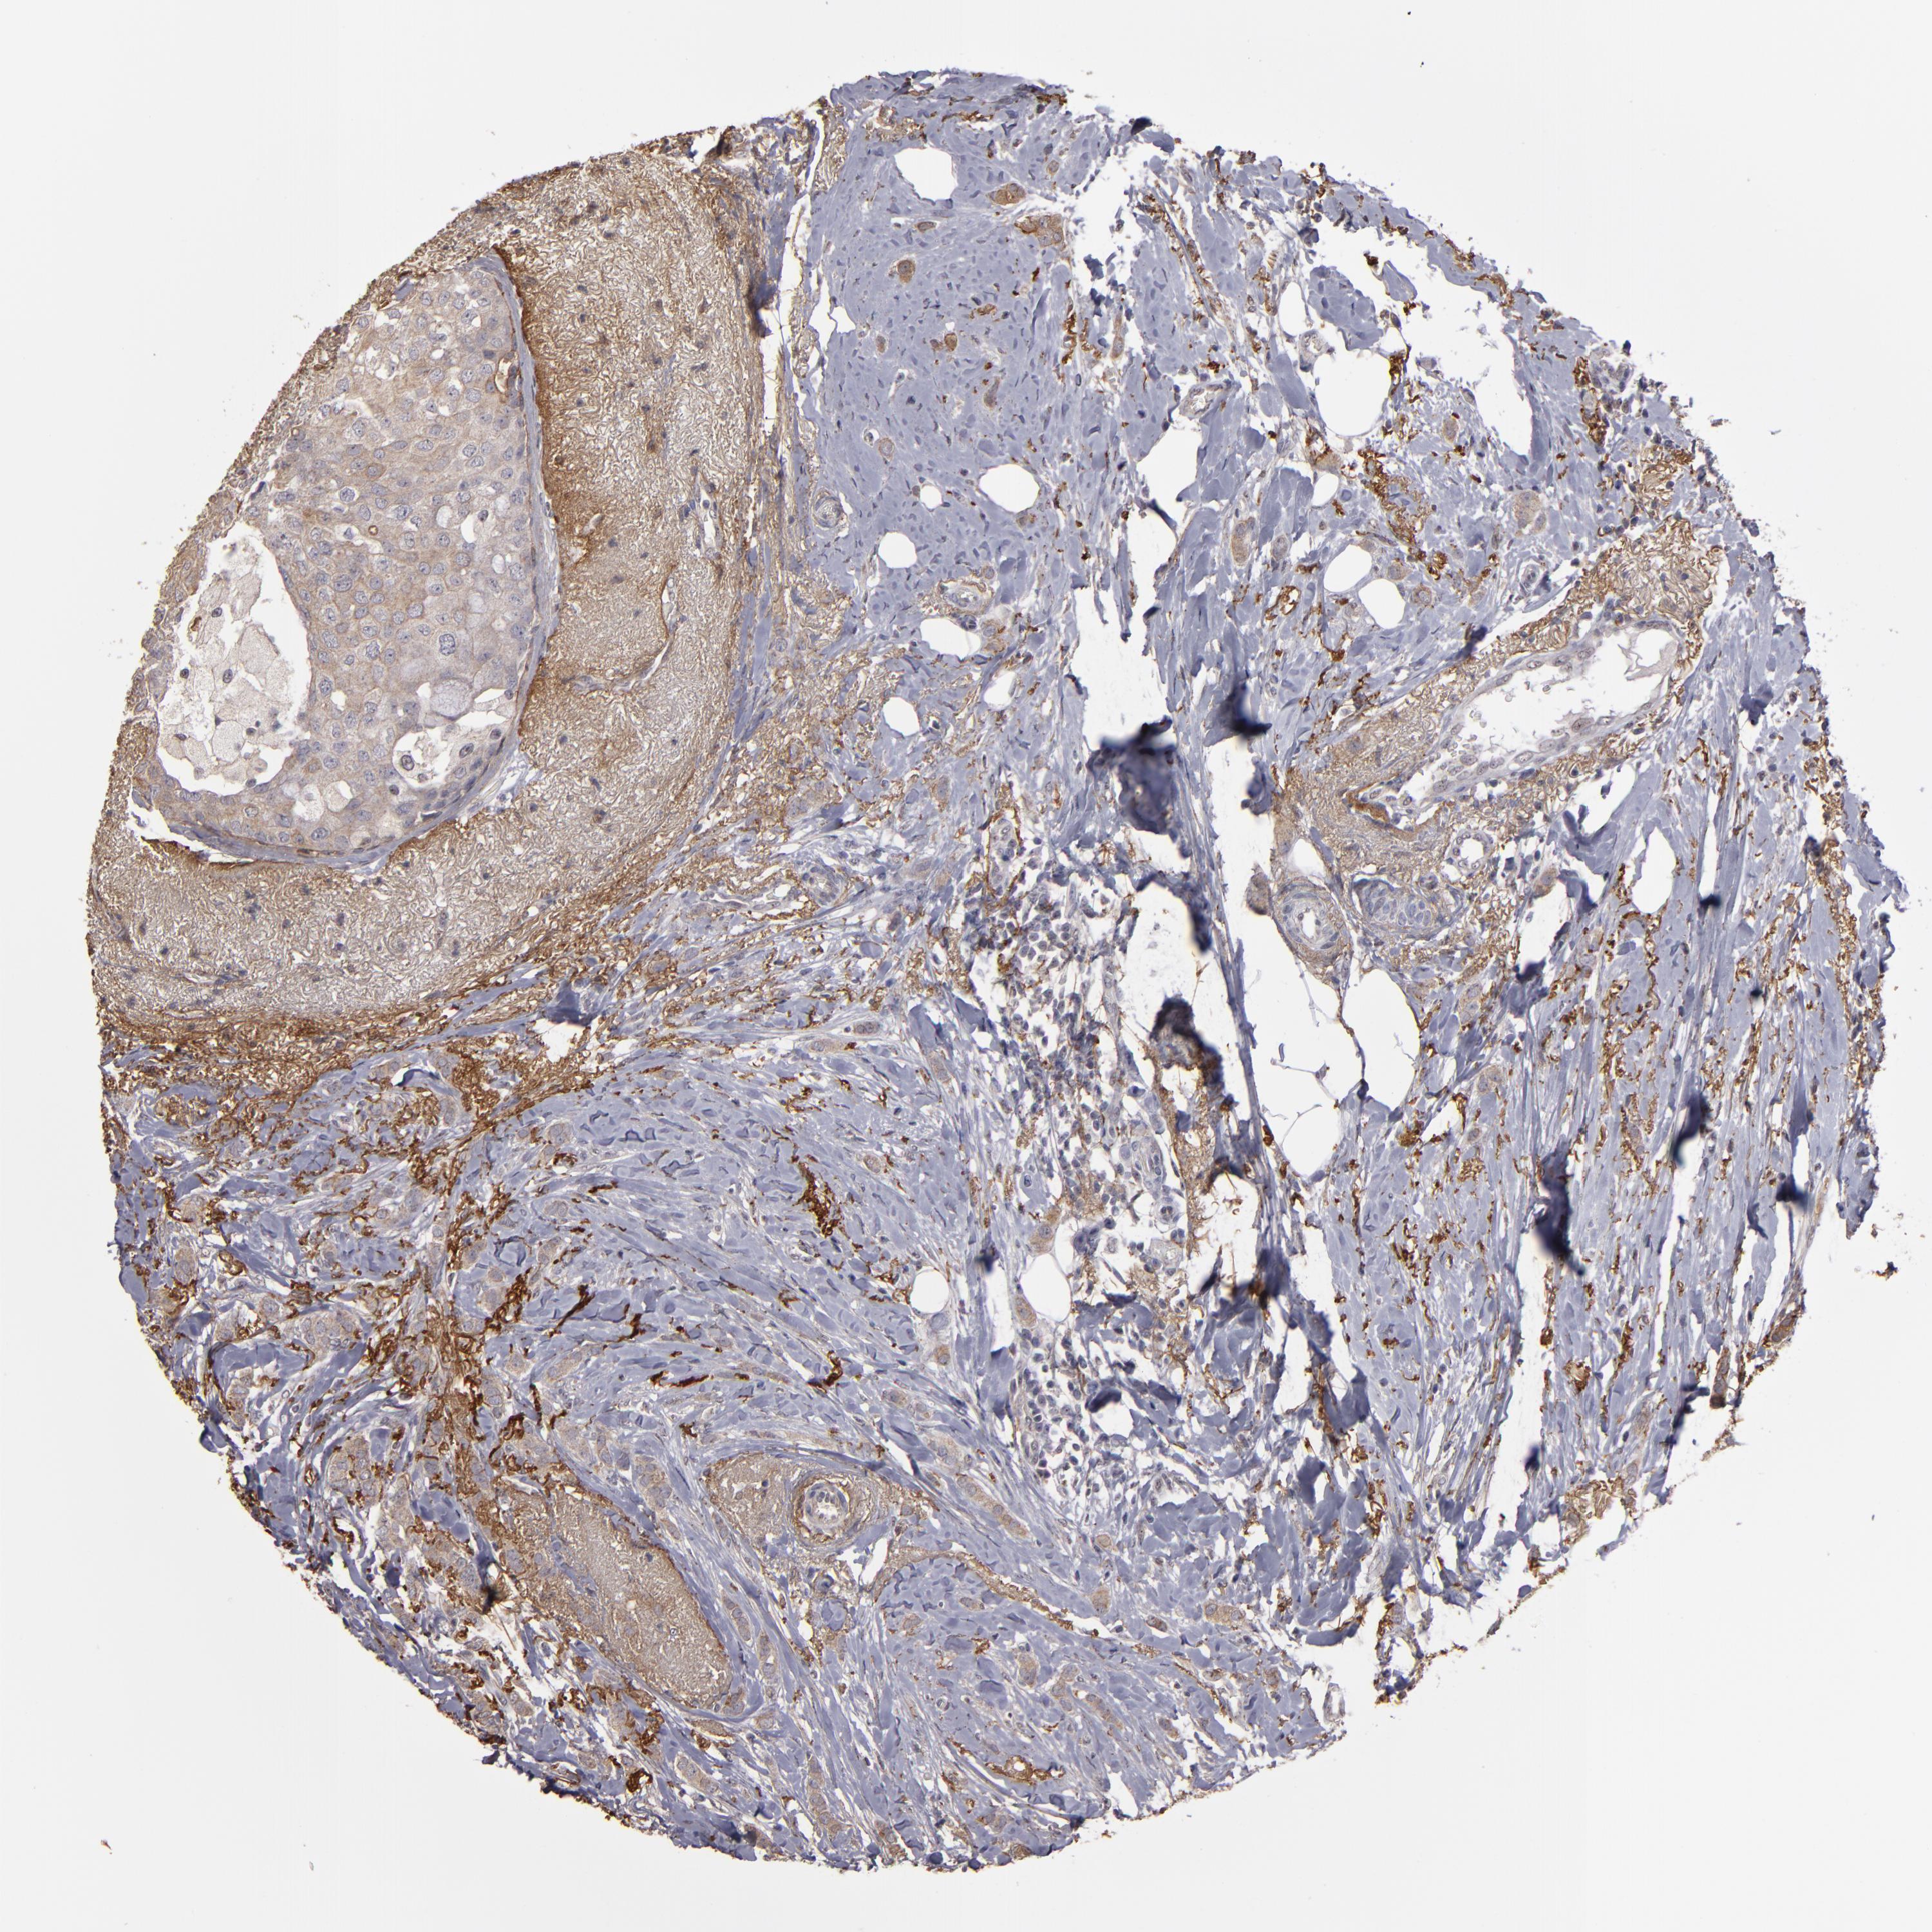

CANCER BREAST CANCER Show tissue menu

BRCA TCGA BRCA VALIDATION PROTEIN EXPRESSION